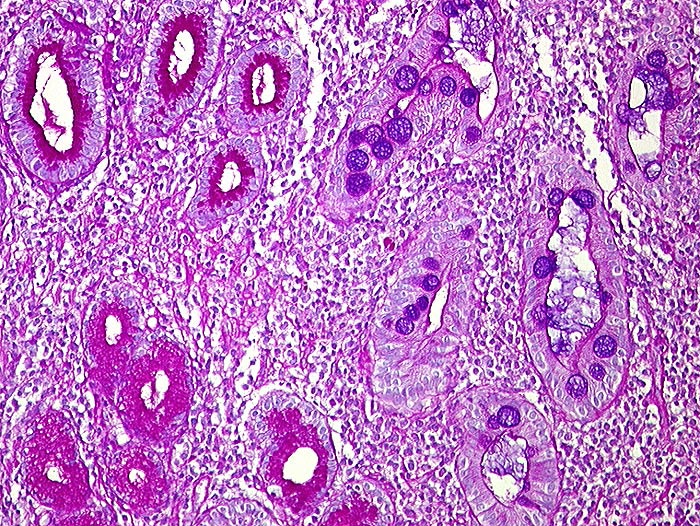

PathoPic ID 1302 - Intestinale Metaplasie

Intestinale Metaplasie

Metaplasie / Heterotopie

Magenantrum

Oesophagus, Magen

Links PAS positive Schleimdrüsen des Magenantrums. Rechts metaplastische Drüsen, welche alcianblaue Becherzellen enthalten. Dicht entzündlich infiltriertes Stroma.

Histologie